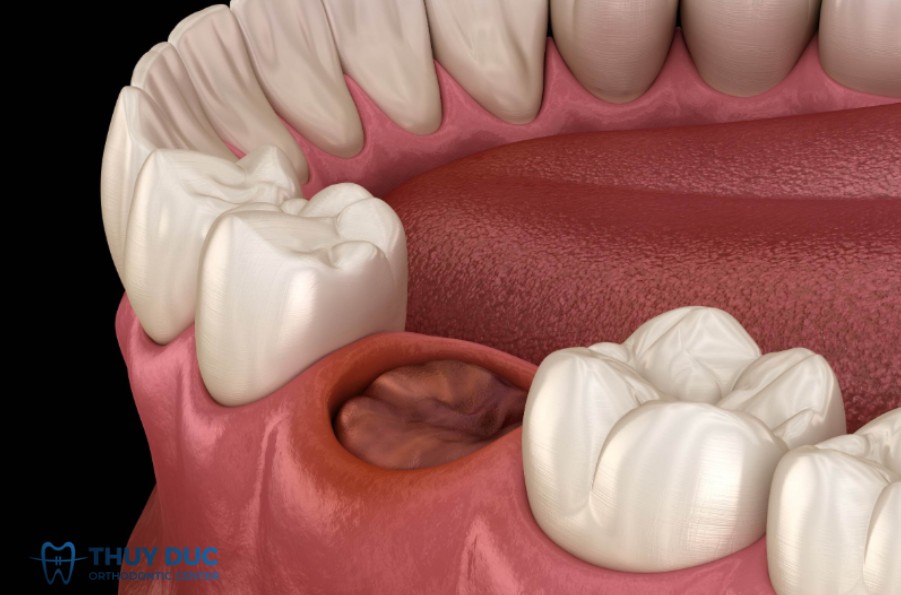

Ổ răng khô

Một biến chứng thường được nhắc tới sau nhổ răng khôn hàm dưới là ổ răng khô – đây là tình trạng huyết khối không hình thành hoặc bị mất sớm ở ổ răng. Nguyên nhân gây ra biến chứng này thường là do huyết khối bị phá vỡ/sổ ra ngoài, xương ổ bị lộ gây đau lan tỏa, chậm lành. Thuốc hút thuốc lá, viêm quanh răng trước khi nhổ, kĩ thuật nhổ phức tạp đều làm tăng nguy cơ (theo tạp chí y khoa Bulgaria).

Trong các nghiên cứu tổng quan, ổ răng khô được ghi nhận với tỉ lệ khá cao ở răng khôn hàm dưới: ví dụ từ 0,5% tới tới 25‑30% tùy nghiên cứu. (PMC)

Khi xảy ra biến chứng ổ răng khô, người bệnh thường cảm thấy cơn đau dữ dội hơn nhiều so với phản ứng sau nhổ thông thường. Cơn đau có thể lan lên vùng tai, thái dương hoặc dọc theo xương hàm, khiến việc ăn nhai và há miệng trở nên khó khăn. Do huyết khối trong ổ răng bị mất, phần xương lộ ra ngoài nên thời gian lành thương thường kéo dài hơn, đồng thời gây khó chịu, hôi miệng và ảnh hưởng đáng kể đến sinh hoạt hàng ngày cũng như chất lượng cuộc sống.

Để phòng ngừa biến chứng ổ răng khô, người bệnh nên được đánh giá và điều trị triệt để tình trạng viêm quanh răng khôn (nếu có) trước khi tiến hành nhổ. Bên cạnh đó, hạn chế hút thuốc lá trong giai đoạn trước và sau phẫu thuật, đồng thời tuân thủ nghiêm hướng dẫn chăm sóc hậu phẫu của bác sĩ – bao gồm giữ vệ sinh miệng đúng cách, tránh súc miệng mạnh hoặc khạc nhổ trong 24 giờ đầu – đều là những yếu tố quan trọng giúp ổ răng hình thành huyết khối ổn định và giảm nguy cơ khô ổ răng.